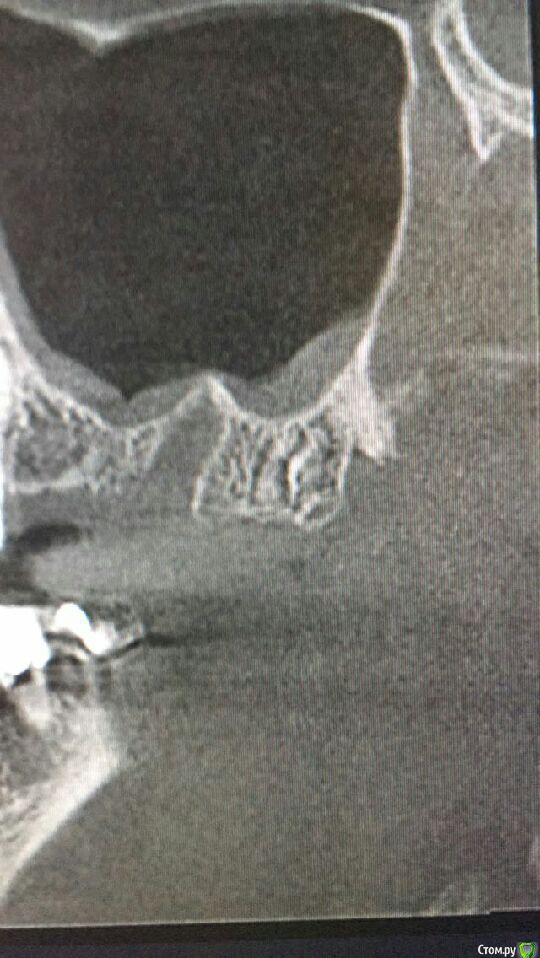

Musya31 Опубликовано 23 января, 2017 Поделиться Опубликовано 23 января, 2017 (изменено) Верх справа. Не помню, чтобы удаляла 8-ку. Это сидит видимо давно. Долго разбираюсь с болями в правой части лица, челюсти. Может быть причина здесь? Нужно удалять, как считаете? И трудным ли будет удаление? Ну и до кучи: нижняя справа семерка. Можно ли попытаться спасти? От нее тоже может болеть? Всем спасибо! Изменено 23 января, 2017 пользователем Musya31 Ссылка на комментарий